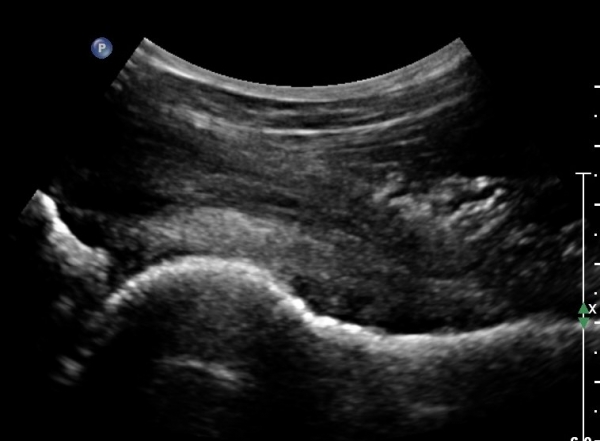

°í°üÀý ¿ÜÃø, ¹Ù·Î µÚ Á¾´Ü¸é°Ë»ç¿Í Ⱦ´Ü¸é °Ë»ç»ó °üÀý ¿Í¼øºÎÀ§¿¡ Ä¿´Ù¶õ °í¿¡ÄÚ ¼®È¸È­°¡ °üÂûµÊ(»çÁø 8, 9)